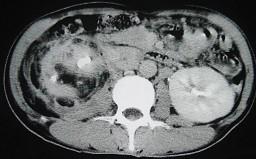

问题 女,43岁,右腰部疼痛不适2年余,加重3天,CT及MR检查如图,应诊断为 ( )

选项 A、右肾脂肪肉瘤 B、右肾海绵状血管瘤 C、右肾错构瘤合并出血 D、右肾脂肪瘤 E、右肾癌

答案 C